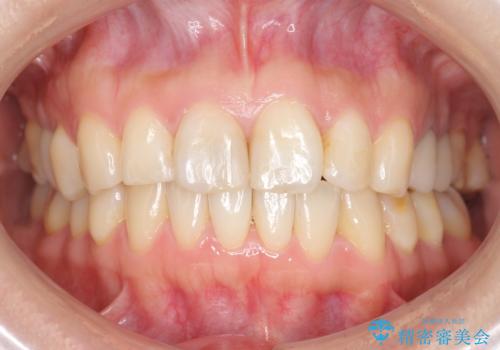

[インビザライン ライト] 短期間(3.5ヶ月)で終わるマウスピース矯正

![[インビザライン ライト] 短期間(3.5ヶ月)で終わるマウスピース矯正の症例 治療後](https://seimitsushinbi.jp/wp/wp-content/uploads/2020/02/2f36cdf472a802b537022ae239b8cb6b-500x350.jpg?v=1580813669)